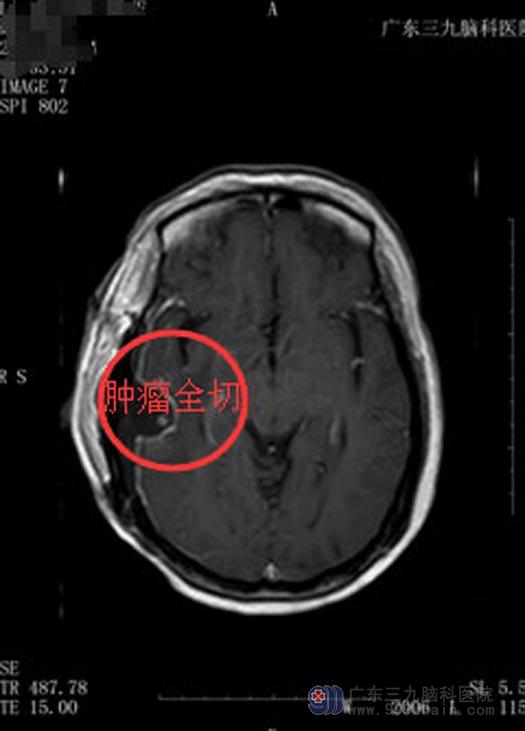

鲁明主任主刀在全麻下行“右侧颞部占位病变切除术”,导航准确定位,术中见病变组织成灰褐色,质软,边界清晰,血供丰富;顺利地将肿瘤分块切除。

手术后